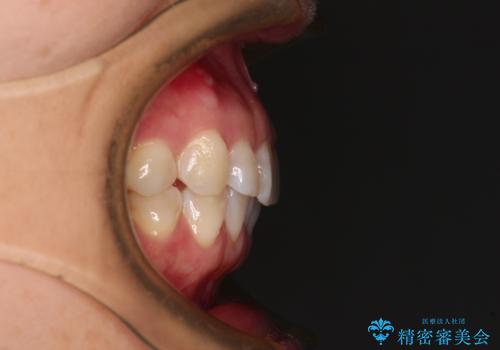

当院では治療前の歯列が整っていない限り、下顎前歯の舌側をワイヤーで固定するようにしています。下顎のみの部分矯正としたことで、マウスピース保定の負担を軽減することができました。

上顎は、失活して歯の色が変色しているため、将来的に補綴治療で自然な口元に仕上げていきたいとのことでした。